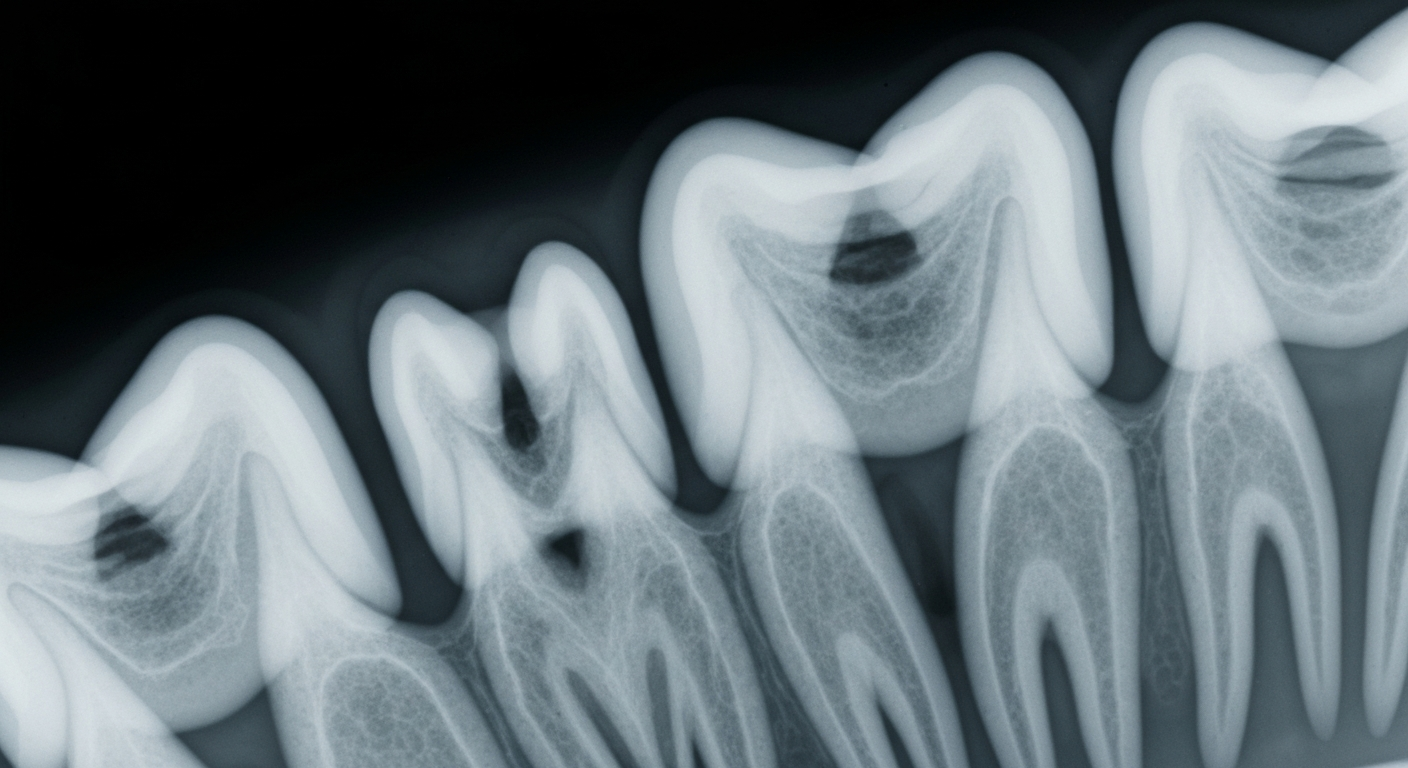

An X-ray view of a human tooth highlights the importance of fluoride for dental health, as Baltimore temporarily reduces fluoride levels in its drinking water due to a nationwide supply shortage.Baltimore TodayThe Baltimore Department of Public Works announced that it will temporarily reduce fluoride levels in the city's drinking water due to a nationwide shortage of the chemical used for water fluoridation. Fluoride levels will decrease from 0.7 milligrams per liter to 0.4 milligrams per liter, but officials say the water will remain safe and the change is not expected to impact public health.

Water fluoridation is a common public health measure to help prevent tooth decay, but the practice has faced growing skepticism in some parts of the country. This shortage highlights the challenges cities can face in maintaining fluoride levels, even as health agencies continue to support the benefits of water fluoridation.